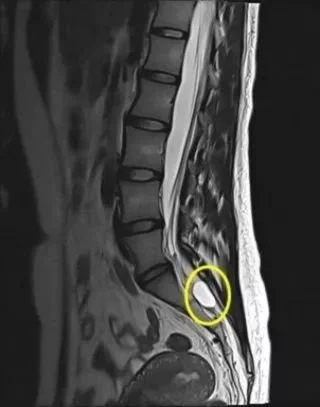

A spinal cyst is simply a synovial cyst that forms on the tendons or joints in the spine, often as the result of natural degeneration. It is a benign, fluid-filled sac that can vary in size and often go unnoticed unless they are pressing against a nerve or affecting joint movement.

Recent advances in imaging have made the diagnosis of spinal cysts more common than in previous years, but they’re still a relatively rare cause of back pain.